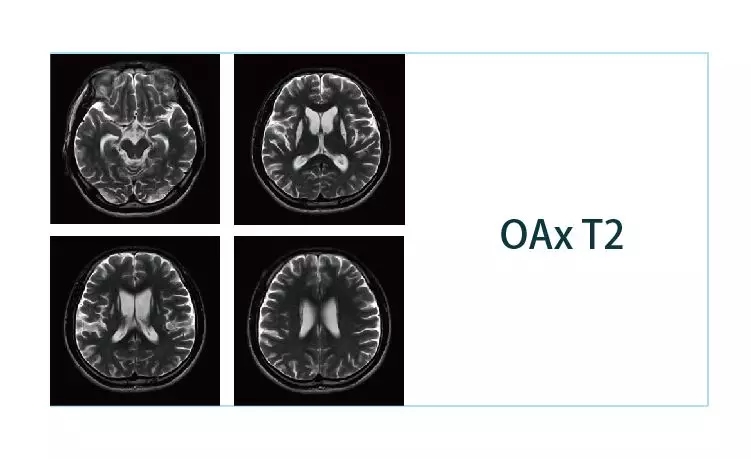

【朗润影像档案】20190216磁共振影像病例结果讨论

【朗润影像档案】20190125磁共振影像病例结果讨论

【朗润影像档案】20190118磁共振影像病例结果讨论

【朗润影像档案】20190111磁共振影像病例结果讨论

【朗润影像档案】20190104磁共振影像病例结果讨论

【朗润影像档案】20181229磁共振影像病例结果讨论

【朗润影像档案】20181221磁共振影像病例结果讨论

【朗润影像档案】20181214磁共振影像病例结果讨论

【朗润影像档案】20181207磁共振影像病例结果讨论

【朗润影像档案】20181130磁共振影像病例结果讨论

【朗润影像档案】20181123磁共振影像病例结果讨论

【朗润影像档案】20181116磁共振影像病例结果讨论